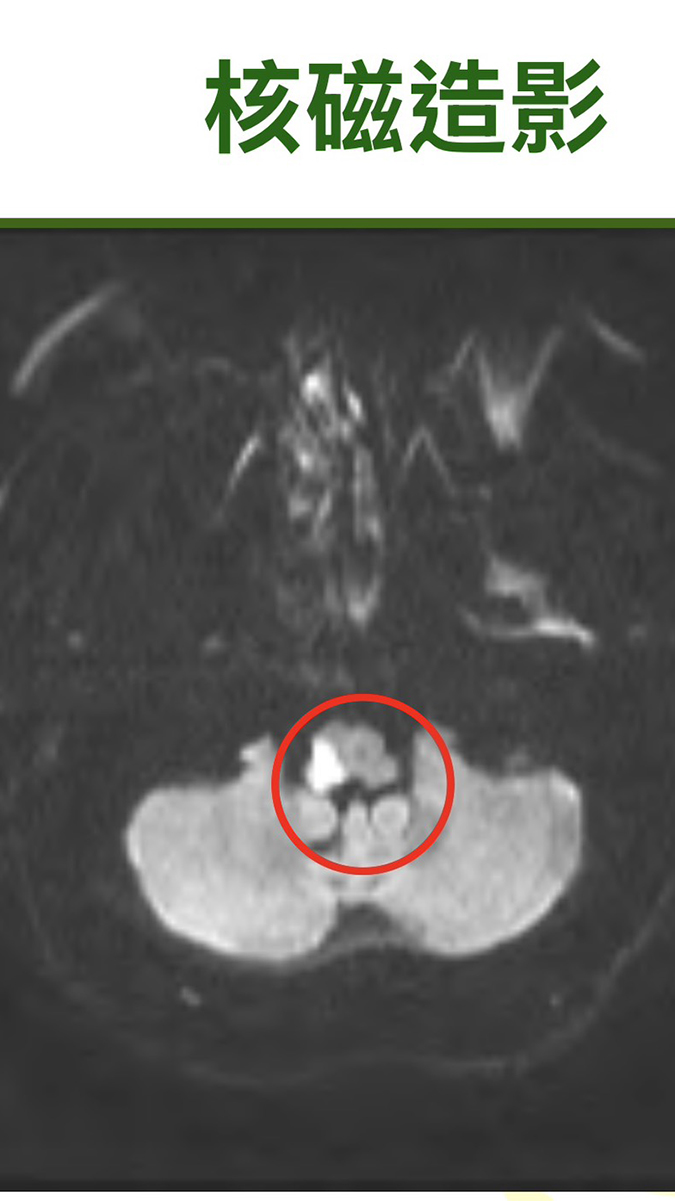

吳醫師指出,患者到院時並無民眾熟知的「臉歪嘴斜、半邊無力、言語不清」等典型中風症狀,只呈現走路不穩。理學檢查顯示四肢無力與視覺問題均正常,但小腦功能測試發現右側距離感辨識異常,因此研判可能為小腦或腦幹中風。進一步核磁共振檢查確認,其腦幹右側及延腦外側出現梗塞。